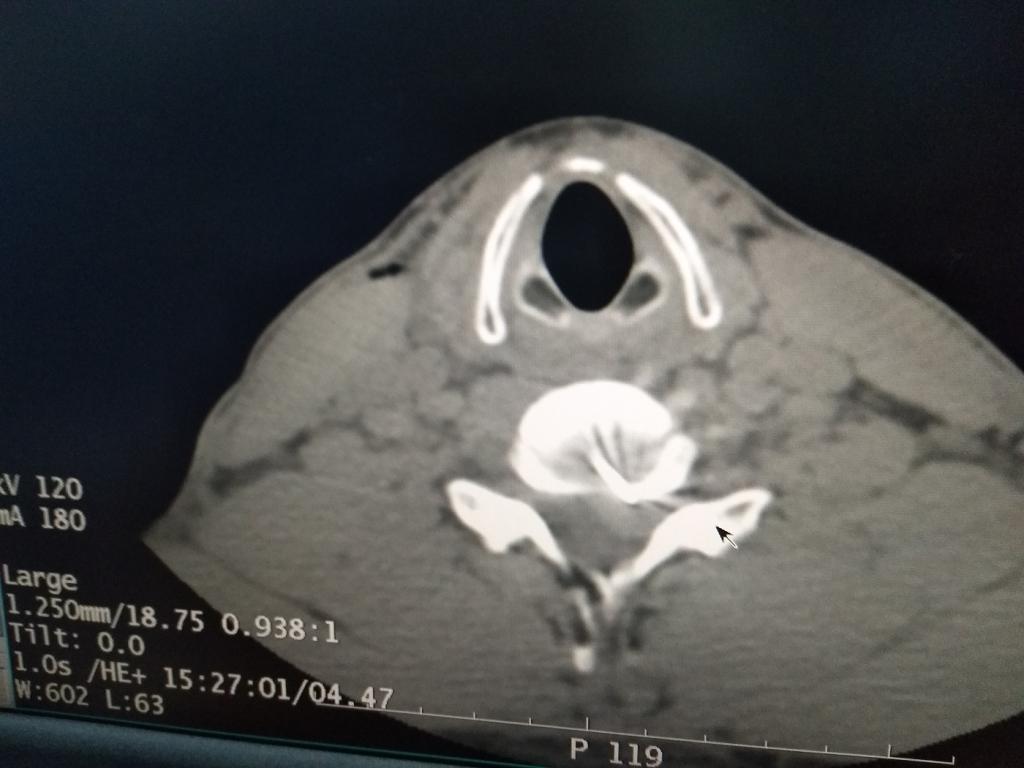

为保证治疗效果,beat365唯一官网第二附属医院疼痛团队在公主任带领下制定了详细的治疗方案,决定采用颈椎低温等离子椎间盘髓核消融术进行治疗,同时多管齐下:一方面完善影像学、实验室等检查进一步明确诊断;一方面准备手术同时对小李进行脱水、营养神经等,暂时延缓病情进一步发展,并予颈椎旁神经阻滞治疗,改善神经根周围组织循环,减轻水肿。在手术中,公主任团队利用CT测量软件计算出穿刺点和穿刺角度,用B超引导慢慢地将直径为0.5毫米的穿刺针送到突出物内,CT扫描确认针尖位置准确。置入等离子刀头(刀头不过一根针粗细),调整刀头方向,再次确认位置后开始消融手术。整个手术过程约1小时,术后,小李的肩膀和手不那么疼,特别是手指又能拿筷子了。一个月后,小李恢复得很好,肩膀和手不麻也不痛,手也有了力气。